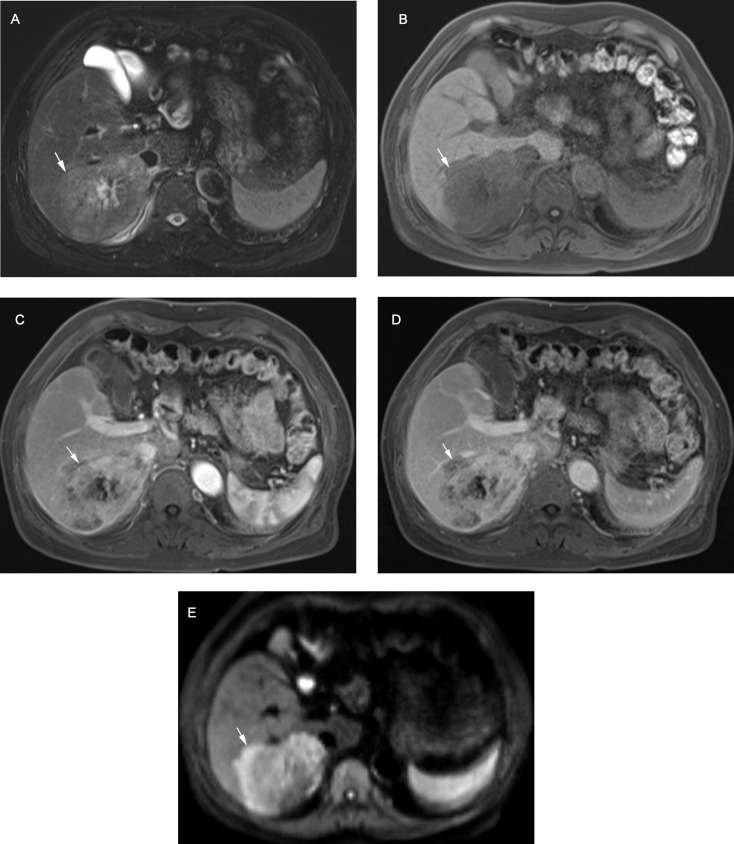

{"title":"Assessment of intrahepatic cholangiocarcinoma with LI-RADS in the high-risk population: MRI diagnosis and postoperative survival.","authors":"Ruofan Sheng, Beixuan Zheng, Yunfei Zhang, Chun Yang, Dong Wu, Jianjun Zhou, Mengsu Zeng","doi":"10.1186/s40644-025-00860-6","DOIUrl":null,"url":null,"abstract":"<p><strong>Background: </strong>The precise impact of LI-RADS-defined risk factors on the diagnosis and prognosis of intrahepatic cholangiocarcinoma (iCCA) remains unclear.</p><p><strong>Objective: </strong>To assess the value of LI-RADS categories and features for iCCA diagnosis, focusing on the diagnostic and prognostic implications of LI-RADS-defined risk factors.</p><p><strong>Methods: </strong>Totally 214 high risk patients, including 107 surgically-confirmed solitary iCCAs and 107 hepatocellular carcinomas (HCC) from two centers were retrospectively enrolled. Clinical and MRI features based on LI-RADS v2018 were compared, and the performance of targetoid features for discriminating iCCA was evaluated. Recurrence-free survival (RFS) was compared across different pathologic diagnoses and LI-RADS categories. Multivariate Cox analysis was performed to identify the independent risk factors for RFS.</p><p><strong>Results: </strong>In the LI-RADS defined high-risk patients, iCCAs differed from HCCs in MRI manifestation. The LR-M category enabled the accurate classification of most iCCAs (89/107, 83.2%), achieving high sensitivity (83.2%), specificity (85.1%), and accuracy (84.1%). The optimal diagnostic performance for iCCA was achieved when at least one targetoid appearance was required for LR-M categorization (AUC = 0.828). Although 26.2% iCCAs presented at least one major feature and 15.0% iCCAs were miscategorized as probably or definitely HCC, only one iCCA case was categorized as LR-5. RFS varied according to both pathologic diagnosis (P = 0.030) and LI-RADS category (P = 0.028), with LI-RADS category demonstrating an independent association with RFS (HR = 1.736, P = 0.033).</p><p><strong>Conclusions: </strong>In high-risk patients, iCCAs frequently exhibit HCC major features, leading to miscategorization as probable HCC. However, the LR-5 category remains highly specific for ruling out iCCA. Furthermore, in high-risk patients with solitary resected iCCA or HCC, LI-RADS category enables the prediction of postsurgical prognosis independently from pathological diagnosis.</p>","PeriodicalId":9548,"journal":{"name":"Cancer Imaging","volume":"25 1","pages":"40"},"PeriodicalIF":3.5000,"publicationDate":"2025-03-26","publicationTypes":"Journal Article","fieldsOfStudy":null,"isOpenAccess":false,"openAccessPdf":"https://www.ncbi.nlm.nih.gov/pmc/articles/PMC11938583/pdf/","citationCount":"0","resultStr":null,"platform":"Semanticscholar","paperid":null,"PeriodicalName":"Cancer Imaging","FirstCategoryId":"3","ListUrlMain":"https://doi.org/10.1186/s40644-025-00860-6","RegionNum":2,"RegionCategory":"医学","ArticlePicture":[],"TitleCN":null,"AbstractTextCN":null,"PMCID":null,"EPubDate":"","PubModel":"","JCR":"Q2","JCRName":"ONCOLOGY","Score":null,"Total":0}

Results: In the LI-RADS defined high-risk patients, iCCAs differed from HCCs in MRI manifestation. The LR-M category enabled the accurate classification of most iCCAs (89/107, 83.2%), achieving high sensitivity (83.2%), specificity (85.1%), and accuracy (84.1%). The optimal diagnostic performance for iCCA was achieved when at least one targetoid appearance was required for LR-M categorization (AUC = 0.828). Although 26.2% iCCAs presented at least one major feature and 15.0% iCCAs were miscategorized as probably or definitely HCC, only one iCCA case was categorized as LR-5. RFS varied according to both pathologic diagnosis (P = 0.030) and LI-RADS category (P = 0.028), with LI-RADS category demonstrating an independent association with RFS (HR = 1.736, P = 0.033).

Conclusions: In high-risk patients, iCCAs frequently exhibit HCC major features, leading to miscategorization as probable HCC. However, the LR-5 category remains highly specific for ruling out iCCA. Furthermore, in high-risk patients with solitary resected iCCA or HCC, LI-RADS category enables the prediction of postsurgical prognosis independently from pathological diagnosis.